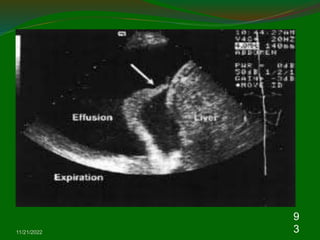

Pleural effusion.

11/21/2022